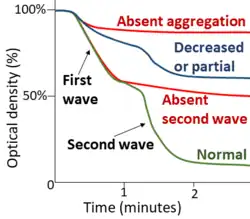

- Platelet aggregation function study:

| [8] | Absent second wave | Partial | ||

| Aspirin or aspirin-like disorder | Absent second wave | Absent | Normal | |